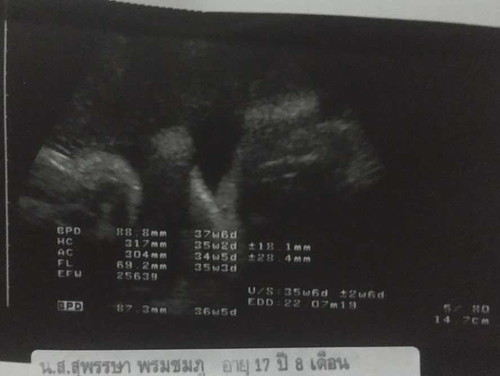

ช่วยดูหน่อยค่ะเพศอะไร

อยากรู้ว่าได้ผชหรือผญดูตรงไหนค่ะช่วยดูช่วยบอกหน่อยค่ะ

แม่ดูว่าน้องนั่งแล้วยกมือขึ้นมา มองไม่รู้ว่าเพศอยู่ตรงไหนค่ะ